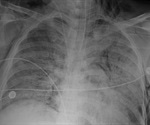

Study links barotrauma to COVID-19 in younger patients